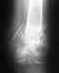

Никаких проблем на снимке не видно. Либо это сильный ушиб, либо проблема в другом месте.